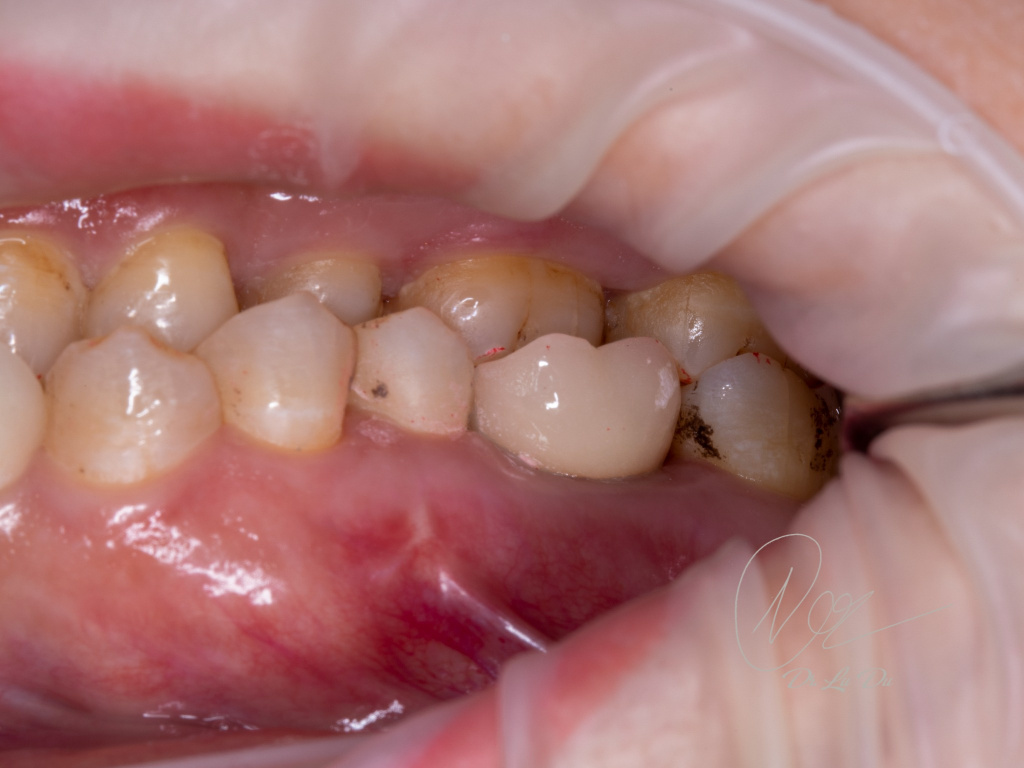

Имплантация AnyRidge с двусторонним закрытым синус-лифтингом.

Осложнения: правосторонний гайморит.